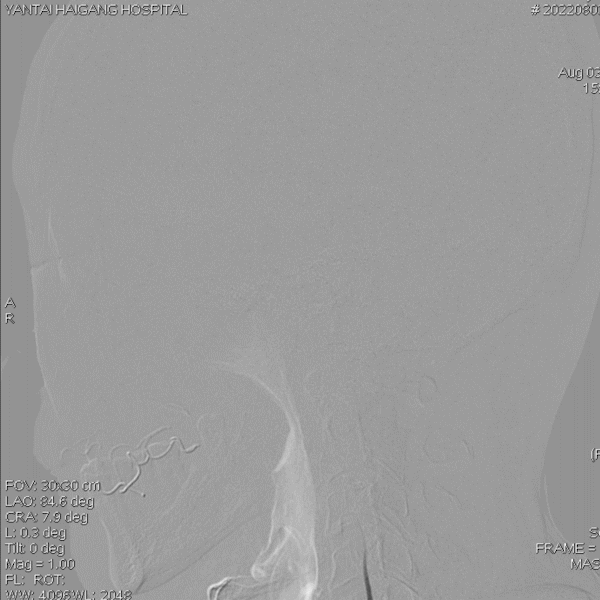

术前造影:

左椎动脉+左颈动脉造影:

右椎动脉造影:

右颈动脉造影:

右椎动脉动脉正侧位: